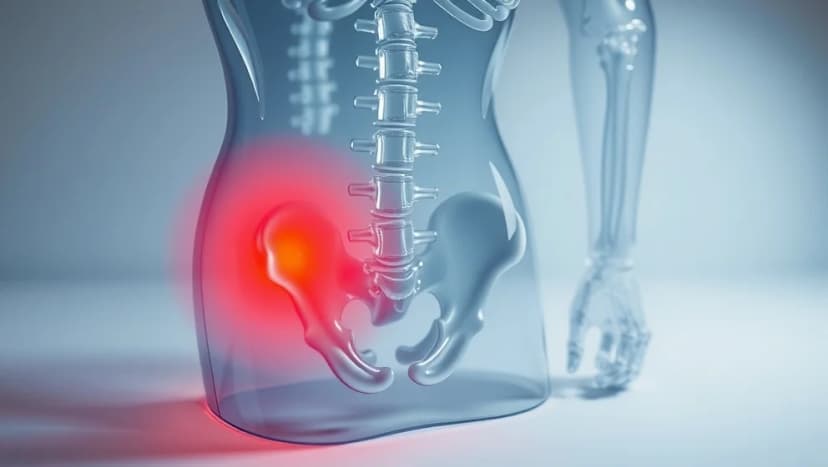

Ont långt ner på vänster sida av magen kan komma från många olika saker. Vi går igenom de vanligaste orsakerna och vad du kan göra själv för att må bättre.

Ont i magen behöver inte betyda något farligt! Du får veta vad som kan orsaka smärtan och hur du blir av med den snabbt.